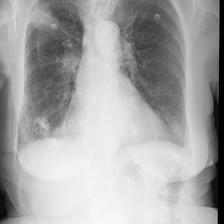

A.1 Qualitative analysis of generated reports

| Reference (by radiologist) | BioViL | BioViL-T |

|---|---|---|

| No evidence of acute cardiopulmonary process. Decreased right pleural effusion. | Small right pleural effusion. | Small right pleural effusion, decreased since _. |

| No relevant change as compared to the previous image. No evidence of pneumonia or other parenchymal pathology. Normal size of the heart. No pleural effusions. | In comparison with the study of _, there has been placement of a right ij port - a - cath that extends to the lower svc. No evidence of post procedure pneumothorax. The cardiac silhouette is within normal limits and there is no vascular congestion or pleural effusion. There is some asymmetry of opacification at the bases, more prominent on the left. In the appropriate clinical setting, this could possibly represent a developing consolidation. | As compared to the previous radiograph, no relevant change is seen. The lung volumes are normal. Normal size of the cardiac silhouette. Normal hilar and mediastinal structures. No pneumonia, no pulmonary edema, no pleural effusions. |

| No previous images. The cardiac silhouette is within normal limits and there is no evidence of vascular congestion, pleural effusion, or acute focal pneumonia. | In comparison with the study of _, there is little change and no evidence of acute cardiopulmonary disease. No pneumonia, vascular congestion, or pleural effusion. | No previous images. The cardiac silhouette is within normal limits and there is no vascular congestion, pleural effusion, or acute focal pneumonia. |

Table A.1 shows example reports generated with BioViL-T and BioViL models, which are compared to the reference radiologist’s reports. In comparison with BioViL which only models the current image, BioViL-T shows the benefit from incorporating prior study information and is able to provide factually more accurate reports especially in terms of describing temporal progression of the findings. This is showcased in the first two examples in the table: In the first row, BioViL-T is able to comment on not only the presence of the pleural effusion but also its improvement while BioViL fails to mention the change. In the second example, BioViL-T is able to correctly identify that there is no relevant change by comparing with the previous study, while BioViL wrongly hallucinates the tube in the current image as a new placement. BioViL-T can also avoid hallucination of the temporal information when there is no prior study. For instance, in the third example, BioViL-T correctly acknowledges that there is no prior image and generates the report based on information from the single current image, while BioViL hallucinates a non-exisistent prior study and wrongly generates temporal descriptions in the report.